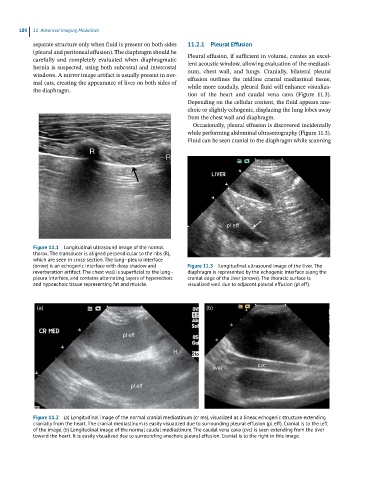

(arrow) is an echogenic interface with deep shadow and Figure 11.3 Longitudinal ultrasound image of the liver. The

reverberation artifact. The chest wall is superficial to the lung– diaphragm is represented by the echogenic interface along the

pleura interface, and contains alternating layers of hyperechoic cranial edge of the liver (arrows). The thoracic surface is

and hypoechoic tissue representing fat and muscle. visualized well due to adjacent pleural effusion (pl eff).

Figure 11.1 Longitudinal ultrasound image of the normal

thorax. The transducer is aligned perpendicular to the ribs (R),

which are seen in cross-section. The lung–pleura interface

Figure 11.2 (a) Longitudinal image of the normal cranial mediastinum (cr ms), visualized as a linear, echogenic structure extending

cranially from the heart. The cranial mediastinum is easily visualized due to surrounding pleural effusion (pl eff). Cranial is to the left

of the image. (b) Longitudinal image of the normal caudal mediastinum. The caudal vena cava (cvc) is seen extending from the liver

toward the heart. It is easily visualized due to surrounding anechoic pleural effusion. Cranial is to the right in this image.